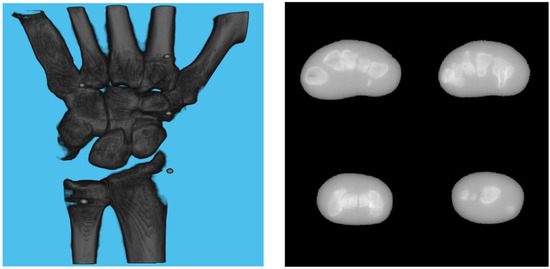

3.1. Simulation Setup

3.2. Effect of Board Thicknesses and Marker Sizes on Reconstructed Image Quality